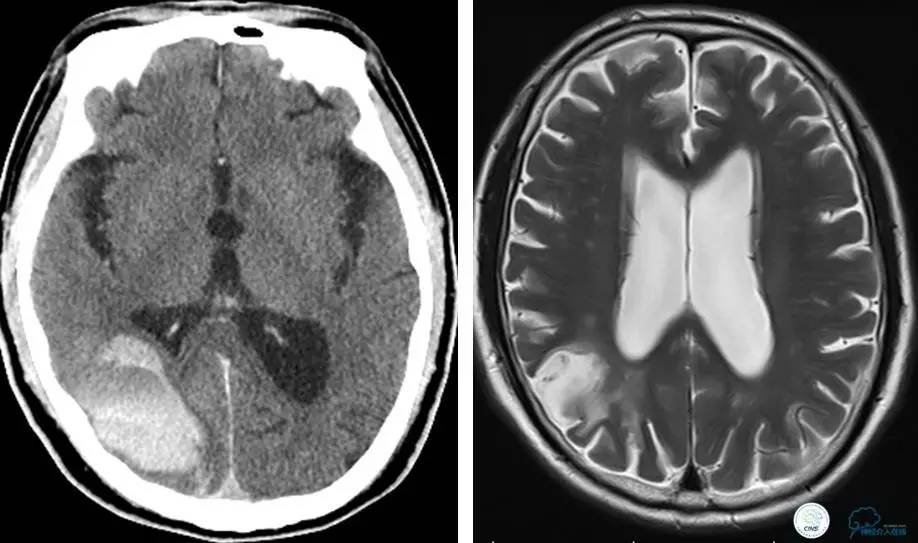

患者:49岁男性,左侧偏瘫1个月,药物治疗、康复训练效果不好,转我院,肌力0~1级。

core-clilnical明显不匹配,是介入开通的合适患者。

术后即刻和6天后CT,患者无明显临床症状。